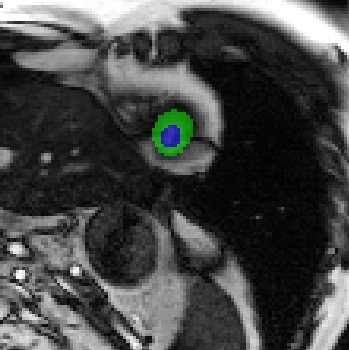

Transformers, the default model of choices in natural language processing, have drawn scant attention from the medical imaging community. Given the ability to exploit long-term dependencies, transformers are promising to help atypical convolutional neural networks (convnets) to overcome its inherent shortcomings of spatial inductive bias. However, most of recently proposed transformer-based segmentation approaches simply treated transformers as assisted modules to help encode global context into convolutional representations without investigating how to optimally combine self-attention (i.e., the core of transformers) with convolution. To address this issue, in this paper, we introduce nnFormer (i.e., Not-aNother transFormer), a powerful segmentation model with an interleaved architecture based on empirical combination of self-attention and convolution. In practice, nnFormer learns volumetric representations from 3D local volumes. Compared to the naive voxel-level self-attention implementation, such volume-based operations help to reduce the computational complexity by approximate 98% and 99.5% on Synapse and ACDC datasets, respectively. In comparison to prior-art network configurations, nnFormer achieves tremendous improvements over previous transformer-based methods on two commonly used datasets Synapse and ACDC. For instance, nnFormer outperforms Swin-UNet by over 7 percents on Synapse. Even when compared to nnUNet, currently the best performing fully-convolutional medical segmentation network, nnFormer still provides slightly better performance on Synapse and ACDC.